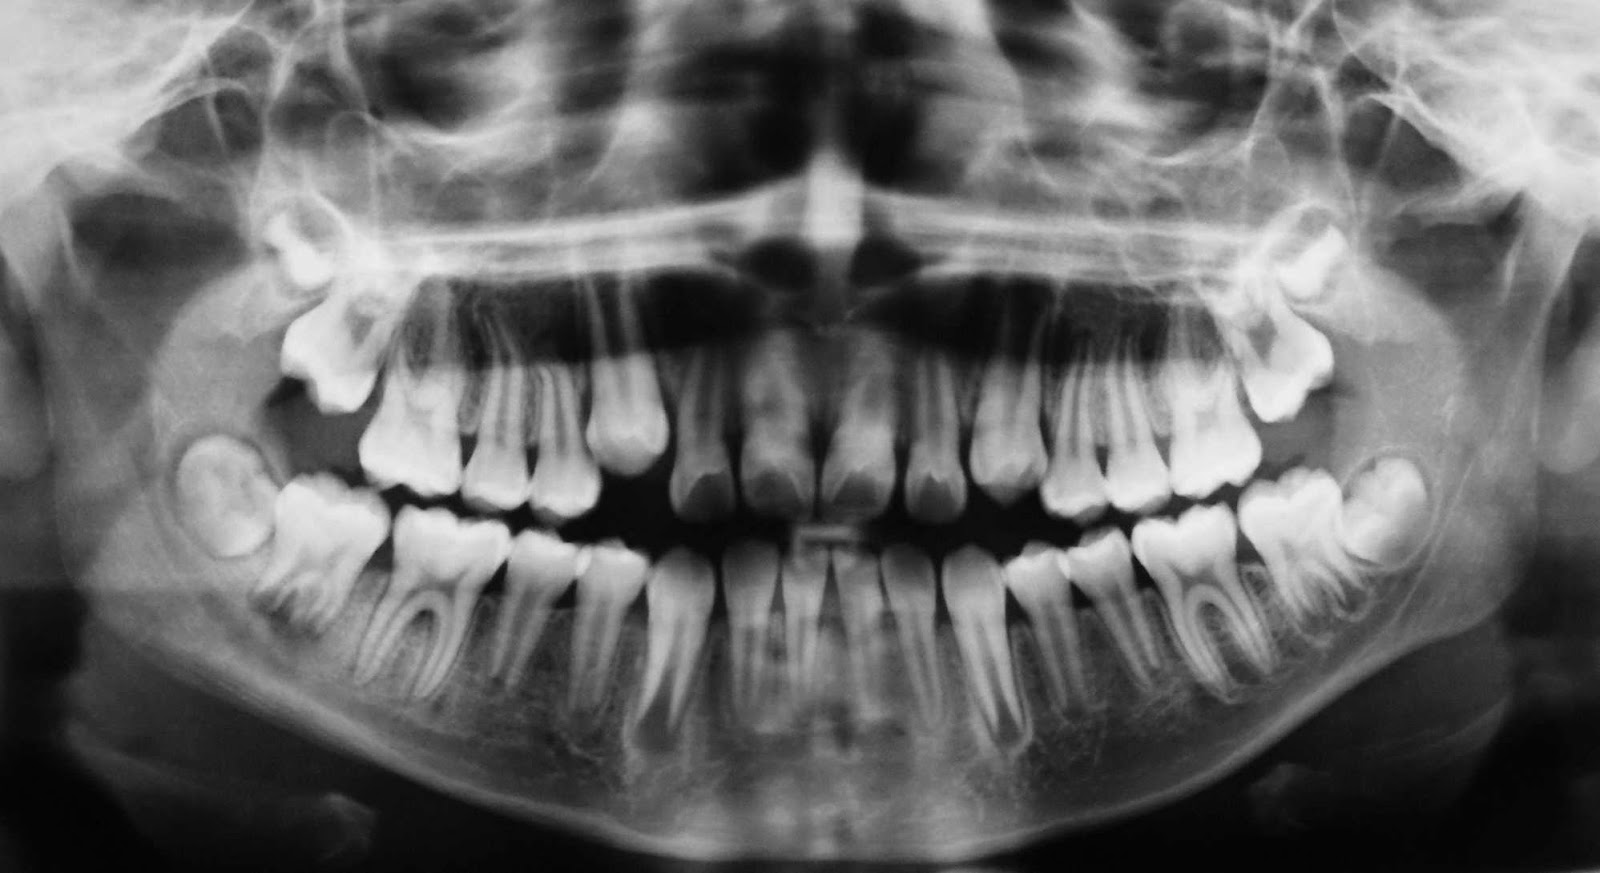

RADIOLOGÍA CONVENCIONAL VS DIGITAL